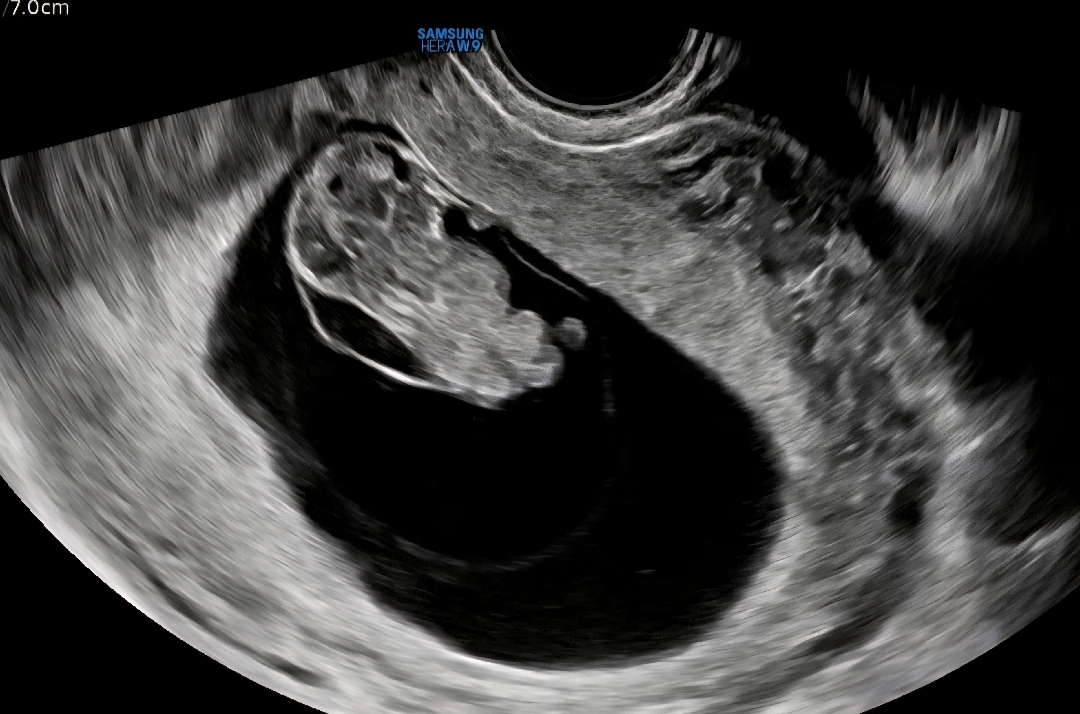

10주2일 됐어용ㅠ 설레는 마음으로 초음파 보러갔는데 목투명대가 4mm로 이맘때 또래보다 많이 두껍다고 ㅎㅊ에서 양모막 검사를 해보라고 하더라구요.. 이거 들어만 봤는데 막상 저에게 닥치니까 너무 슬펐어요 그러고 집에와서 엄청 검색하고 보니.. 10주면 목투명대 보기엔 이르다고 하는 글을 봐서 조금은 희망회로 돌리게되네요? 그래도 의사선생님이 말씀하신거라 확실히 문제가 있는걸까 싶기도 하고요ㅠㅠㅠ 일단 10주차라 융모막검사를 아직은 못해서 다음주로 병원 예약했어용.. 담주 병원에서 다시 봤을땐 목투명대가 얇아졌음 좋겠네요ㅠㅠㅠ 제발 아무일도 아니었음 좋겠어요.. 목투명대.. 많이 두꺼워 보이죵?ㅠㅠㅠ